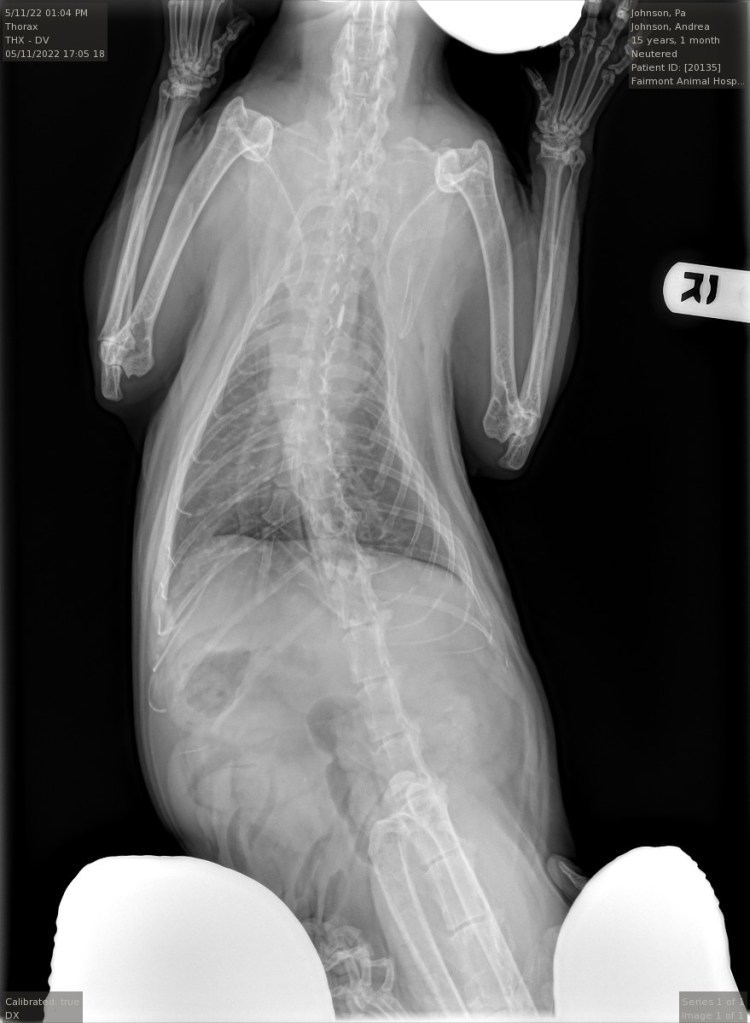

The tech took him to the back then the vet came out a few minutes later, looking subdued. She said that his heart sounded quite bad, and that he was receiving oxygen. I consented to an Xray.

This revealed severe pleural effusion – fluid collected around the membranes that surround the lungs. It was intense enough that his heart was mostly obscured. This was exactly what brought Grey Guy to the end, too(May 6, 2019). This is is usually the result of traumatic injury, cancer or heart failure. The vet was patient and kind as she explained what she saw on the Xrays, and told me about the possible options – to drain the fluid with a large needle, then aggressive treatment with diuretics, and overnight stays in the ER hospital in the oxygen chamber. However, the prognosis was really not good, particularly given the severity. The fluid would always come back as it was a symptom of a greater issue. I told her I had been been down this road before, and that I knew that euthanasia was the only kind choice. Since it was probably heart failure (there were no obvious masses on the Xray), and his decline had come on rapidly within the last 5 days, I knew that the probable outcome would be harrowing, like a saddle thrombus. I could tell that today was the worst day he had ever had, since he joined my household.